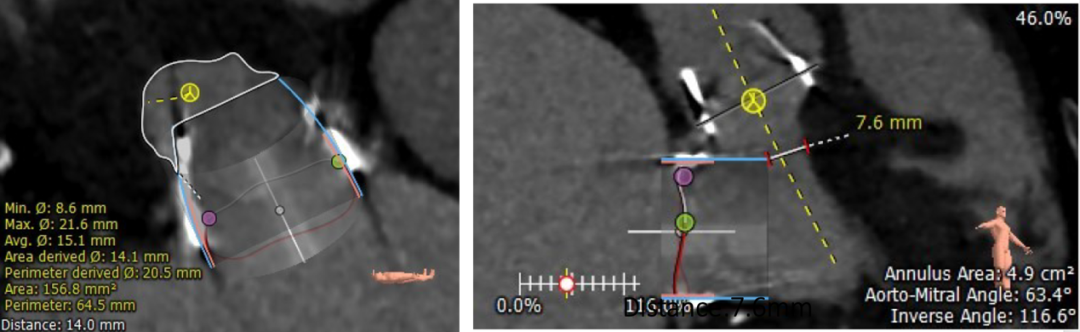

通过CT模拟瓣膜再次植入后效果、植入位置(90/10)。

S3植入效果图

模拟S3植入90/10位置

充分评估左室流出道梗阻风险,测算新LVOT 面积为156.8mm²,直径为7.6mm。

新LVOT测算